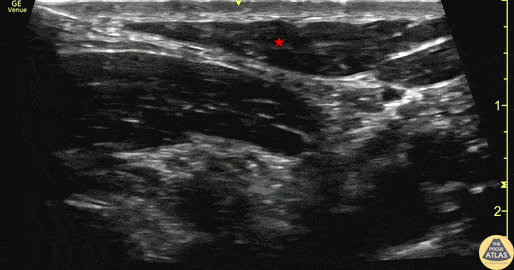

30s M presented with clavicle pain after fall on bike, noted to have obvious deformity to L clavicle, and to be closed and neurovascularly intact. Radiographs confirmed a distal third clavicle fracture, and nonoperative management was recommended by orthopedic surgery. To augment pain control, a superficial cervical plexus block was performed. In these images, the needle is seen entering from the posterior aspect (left of screen), depositing anesthetic in the plane just deep to the sternocleidomastoid muscle (*). The patient had improvement of pain and was discharged with outpatient orthopedic follow up. Dr. Michael Heffler, PGY3 Denver Health Residency in Emergency Medicine